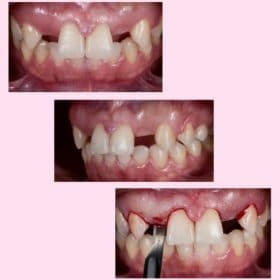

Step 1: Pre-surgical 3D planning.

Step 2: Pre-prosthetic 3D planning.

Step 3: Surgical steps from incision to implant placement.